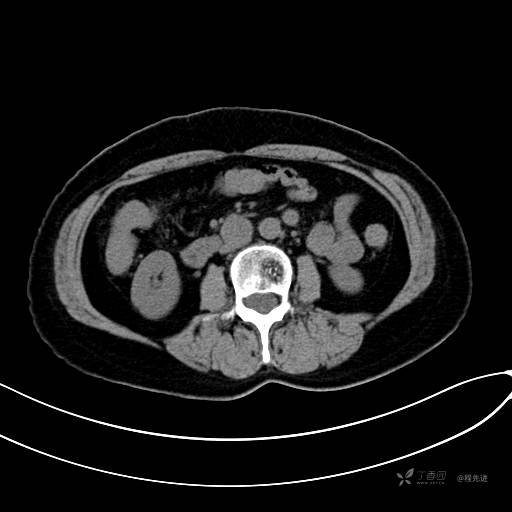

CT平扫